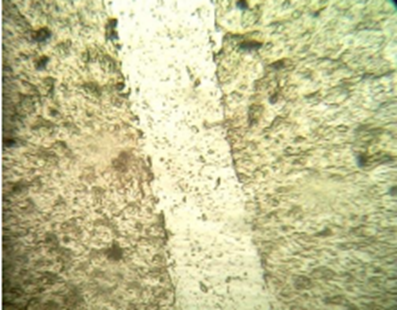

In-vitro scratch assay

Percentage (%) of cells that moved in the direction of the wound and helped it close microscopically images representing the In vitro wound healing nature of Sample: L929 cells were incubated in presence or absence of Samples and standard drug Cipladine and images were captured at 48 hours. According to images and results Sample showed Moderate activity Percentage (%) of cells that moved in the direction of the wound and helped it close.

Figure 2: Normal Morphology of L929

Control - Wound Scratch                                       After 48 hours - Control

Standard - Wound Scratch (Cipladine)                 After 48 hours - Standard (Cipladine)

Sample - Wound Scratch                                 After 48 hours - Sample

Table 2 Percentage (%) of Cells Reduction in Wound Closure.